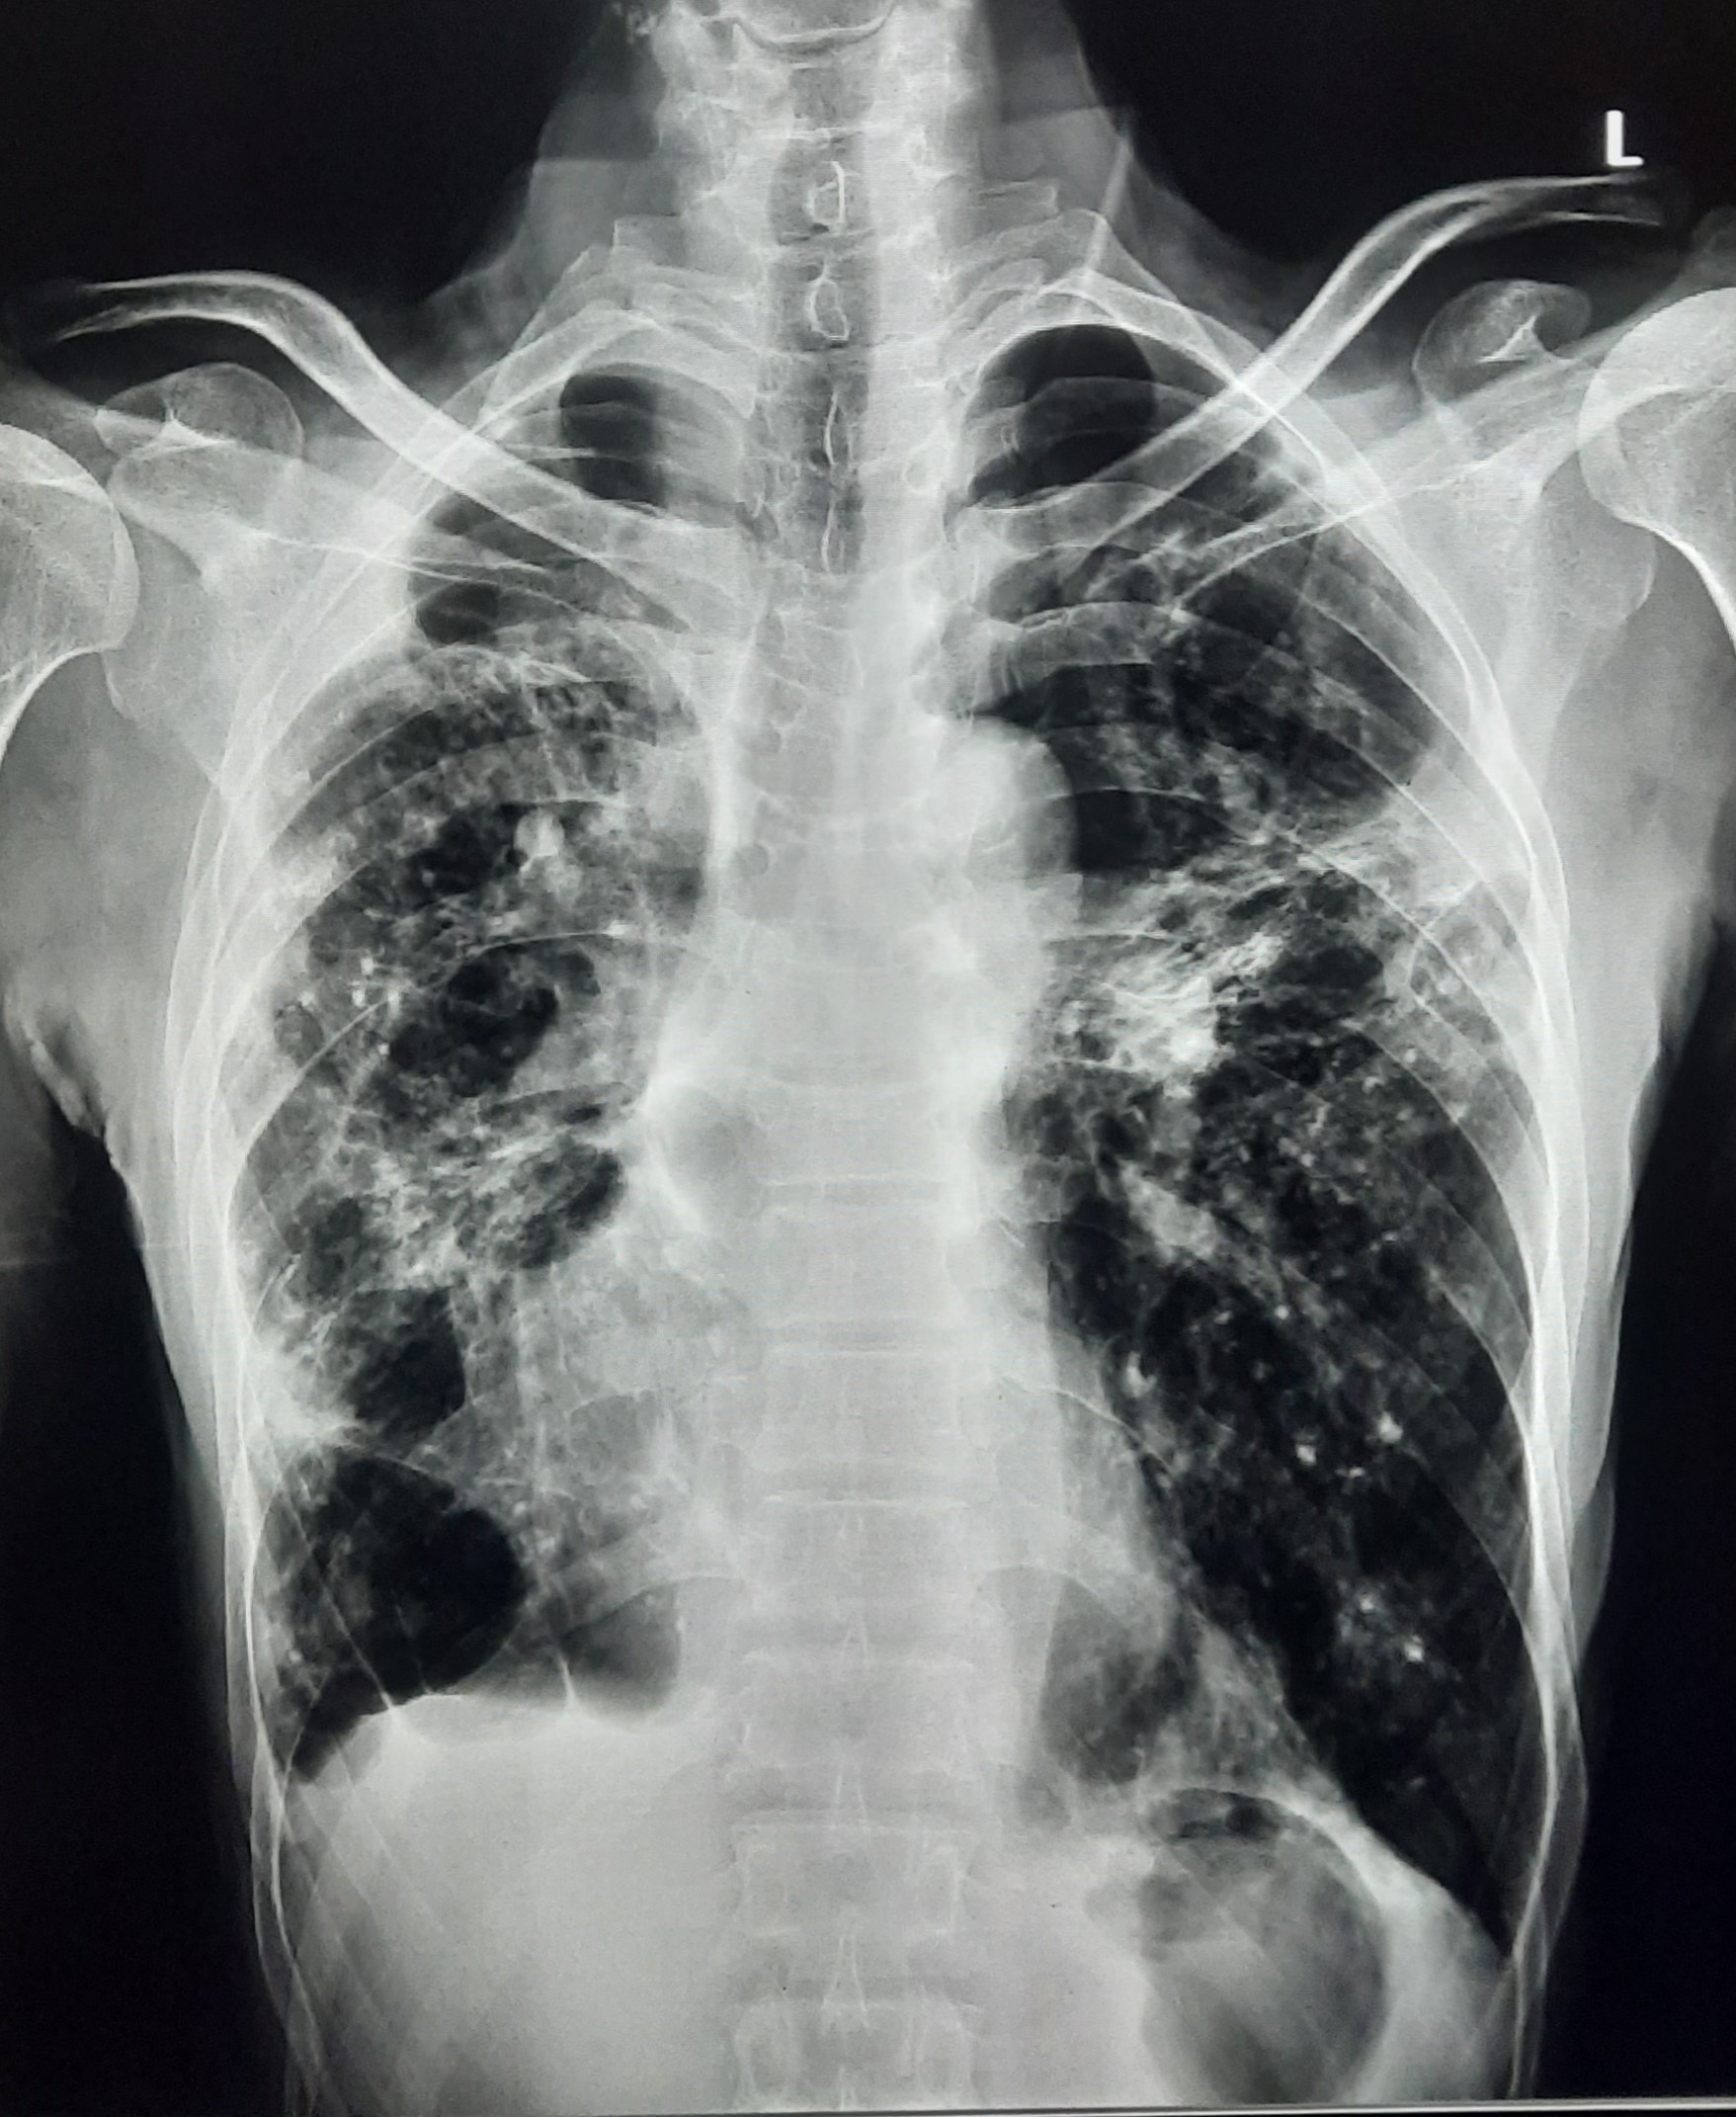

| 132 | IGGMC, Nagpur, Nagpur | P2 | 29-4340 | Ritesh Chaudhary | Consent taken on Paper | 30 Yrs. |

Provisional Diag : Post TB Sequelae

Final Diag : Post TB sequalae With Fibro Cavitary Changes |

Post TB Sequelae | Bilateral Upper Zone Fibro Cavitary Changes With Right Upper Zone Fungal Ball With Bilateral Haziness With Tenting Of Diaphragm | Abnormality visible on x-ray |